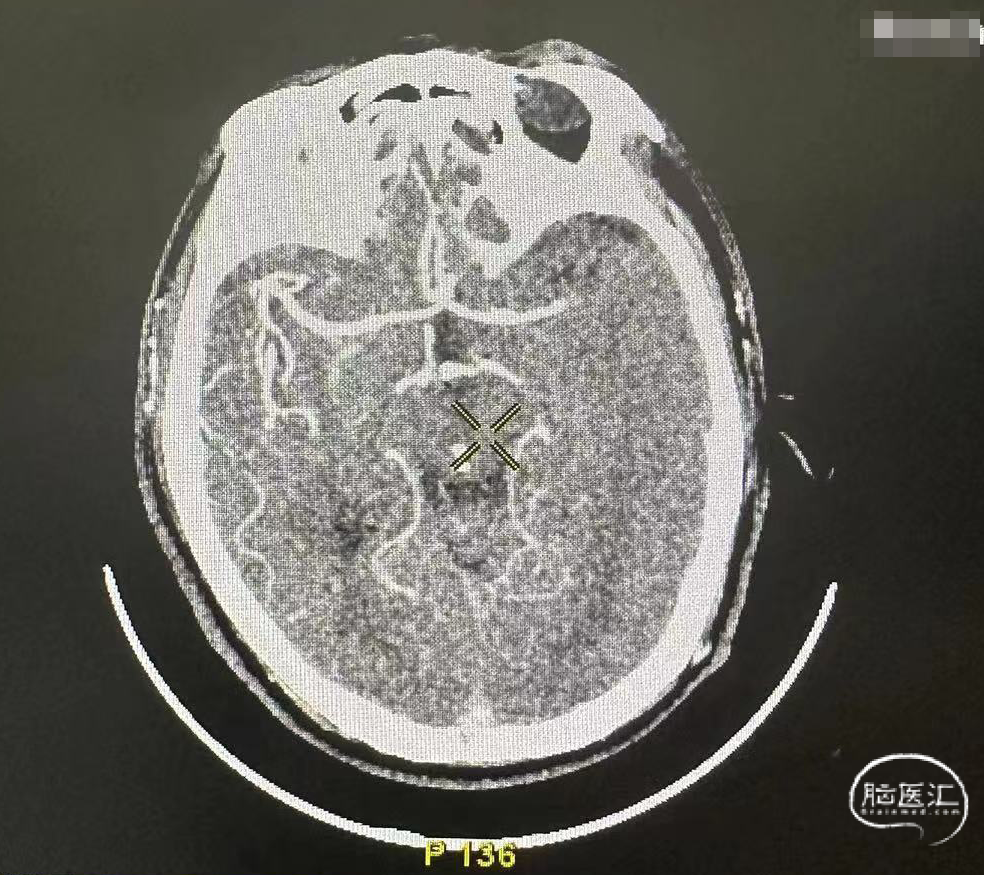

CTA示左侧大脑中动脉闭塞。

造影证实左侧大脑中动脉M1段闭塞。

术中造影确认脑血流完全恢复,mTICI 3级,术后24小时复查头颅CT左顶叶少量渗出。

术后7天后患者NIHSS评分改善。CT提示渗出基本吸收,有部分缺血表现。